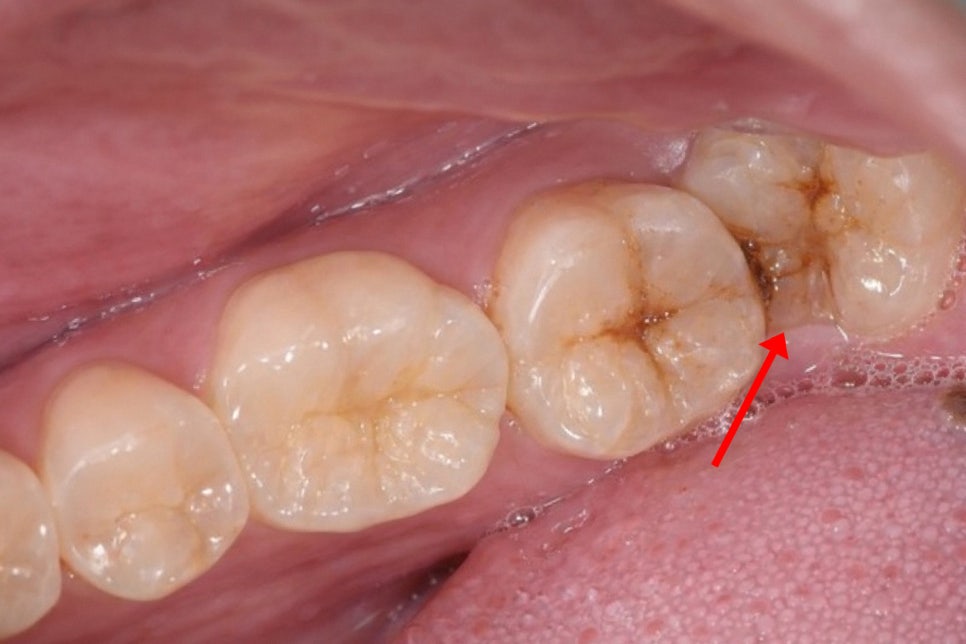

또한 사랑니 주변으로 치관주위염이 발생해

만성 염증을 일으켜 통증 및 출혈이 날 수 있으며

환자가 육안으로 확인하기 어렵고

근관에 근접할 정도로 우식이 깊어지기 전까지는

통증이 없는 경우도 많습니다.

따라서 환자가 시린 느낌이나 통증을 느껴

내원했을 때는 이미 치수의 감염이

진행된 경우가 대다수이며